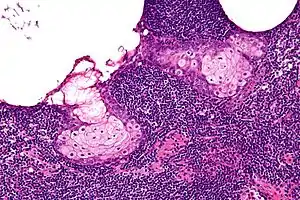

| High magnification micrograph of a sebaceous lymphadenoma. H&E stain. | |